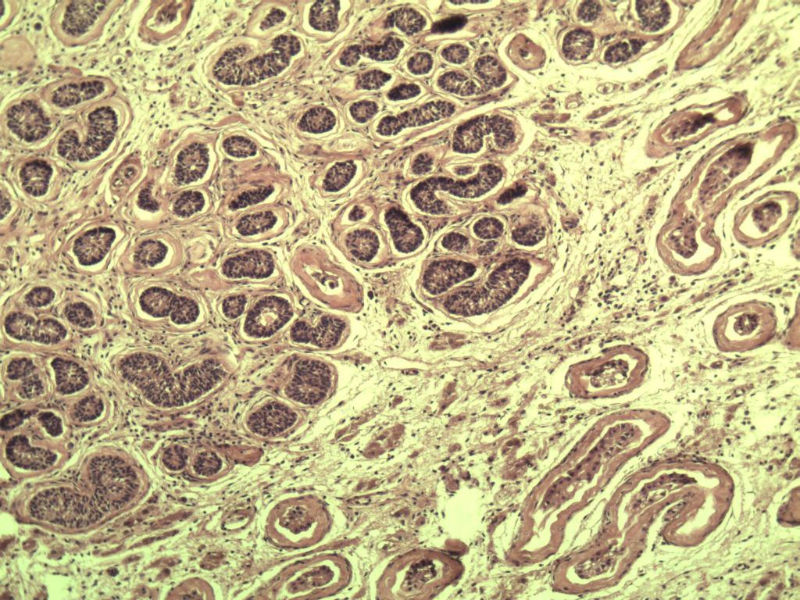

男 27岁 腹腔隐睾 5*3*2 cm, 切面灰红灰黄、实性、质中,请各位老师看看,是精原细胞瘤吗?感觉不像.